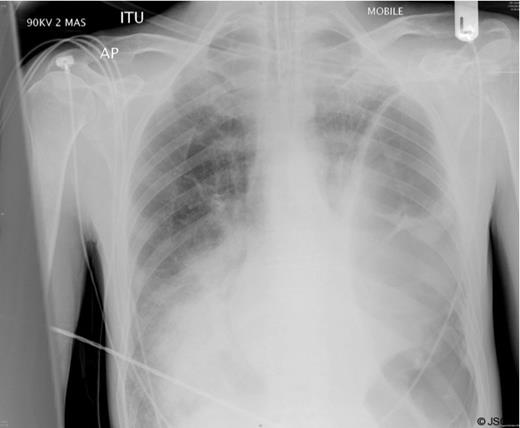

A chest radiograph (Figure 1) showed a large air filled structure within the left hemithorax, loss of clarity of the left hemidiaphragm and patchy consolidation of the middle and right lower lobes.

A clinical diagnosis of a possible spontaneous rupture of the diaphragm was made. The patient underwent an emergency laparotomy as he was not stable enough to undergo cross-sectional imaging to confirm the diagnosis. There were no abnormal findings at laparotomy. A left sided chest drain was immediately inserted with release of air under tension and pus (Figure 2).

In retrospect it is likely that this gentleman presented with a severe pneumonia complicated by a contained tension pneumothorax within an empyema cavity caused by positive pressure ventilation.